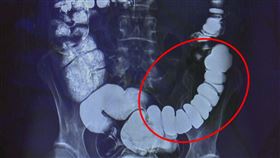

女嚴重便秘飛台灣求救!醫:把腸子逼太緊

嚴重便秘病人跨海返台求醫,台中慈濟醫院大腸直腸外科主...

2023/02/23 10:03